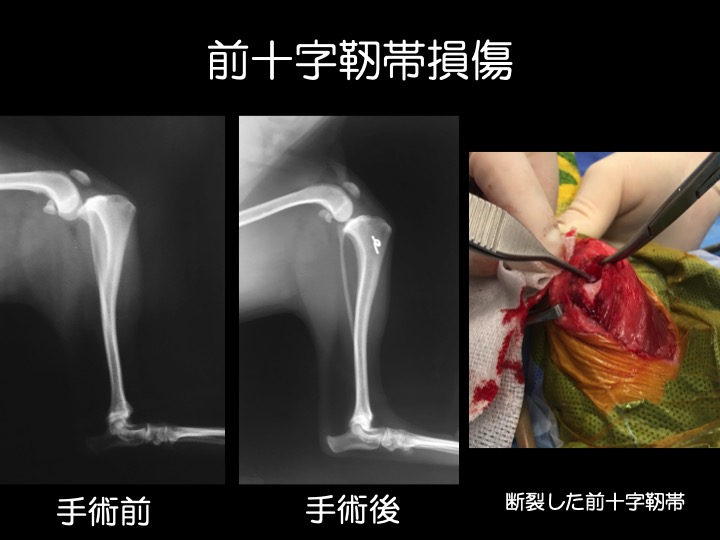

・前十字靭帯は、大腿骨(太ももの骨)と脛骨(スネの骨)を結ぶ靱帯で、大腿骨に対して脛骨が前方に飛び出したり内側にねじれないように支える役割があります。

・肥満、加齢、慢性の膝蓋骨脱臼(特に小型犬)による靭帯の脆弱化などが原因で、前十字靱帯は切れやすくなります。靭帯の損傷によって、痛みや、足を挙げたりかばったような歩き方などが見られます。

・治療は、鎮痛剤などによる内科治療もしくは外科手術となります。手術は、ラテラルスーチャー(関節外制動法)とよばれる、脛骨が前方に変位かつ内旋しないよう膝関節に糸をかける方法を用います。

・中〜大型犬では、より術後早期の回復が期待できる「TPLO(脛骨高平部水平化骨切り術)」という手術を実施している高度医療施設へのご紹介も行なっております。